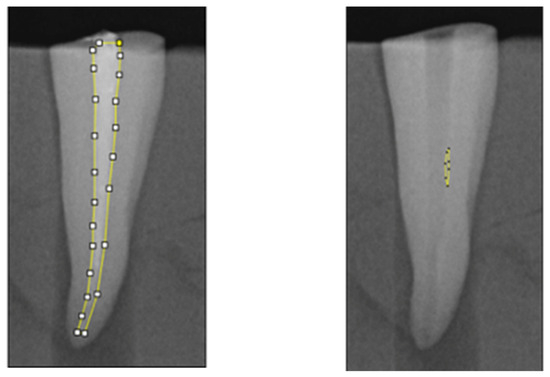

2.4. Radiographical Analysis

Figure 2. Methodology for quantitative analysis of the canal area and residual canal area using ImageJ software on periapical radiographs. A periapical X-ray was taken at the end of the canal obturation. On the digital image obtained, the canal area and the obturation material area were calculated by manually delineating the boundaries of the region of interest. Periapical X-ray image taken at the end of the retreatment. Residual materials are manually highlighted. The obtained image was used to calculate the canal area and the residual area, divided by root thirds.